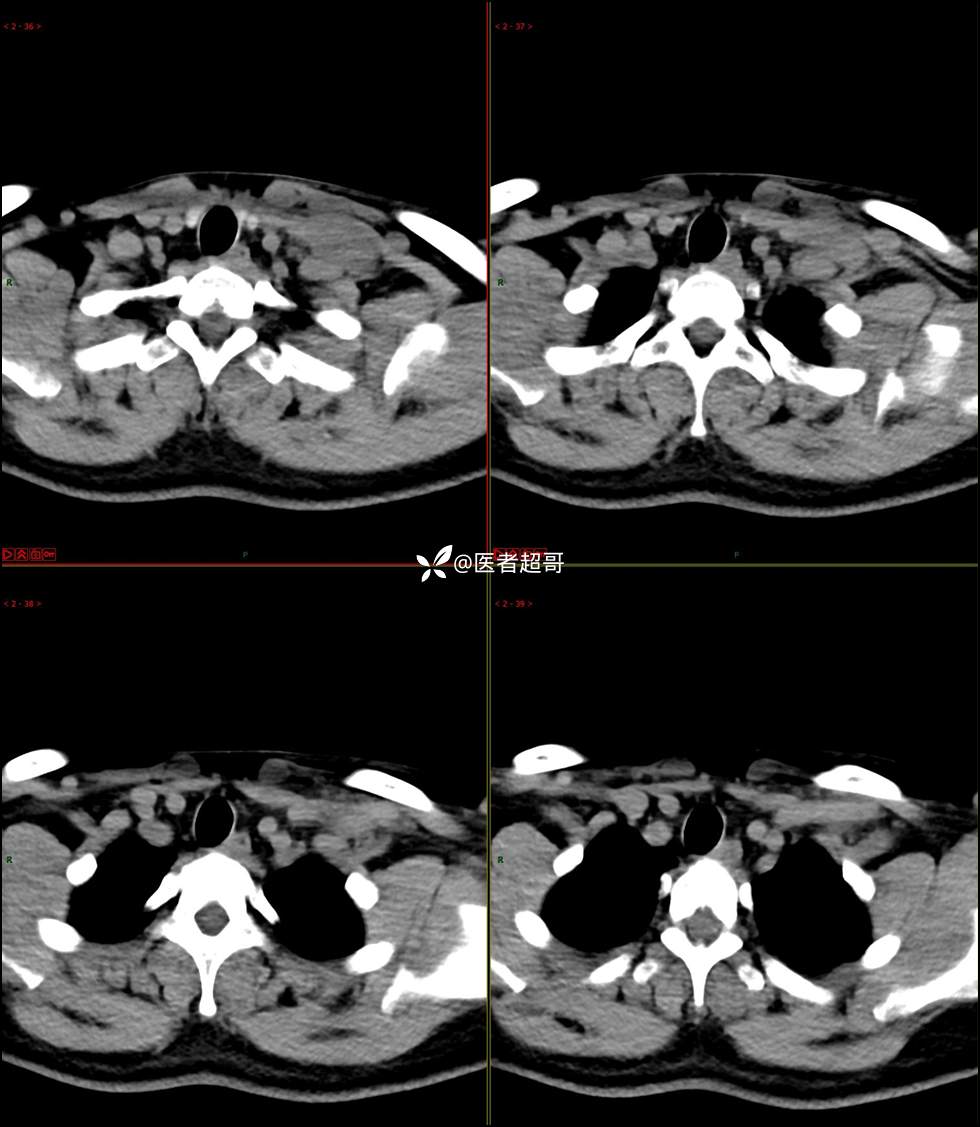

现病史:患者自述10余天前无意中发现左侧颈部一肿物,颈部活动时、进食时伴疼痛,无发热,患者前往人民医院就诊,给予输液治疗(头孢呋辛钠2g bid 硫酸阿米卡星0.4g qd、)10天,患者感肿物轻微变小,后患者为求进一步治疗,昨日来我院门诊就诊,给予颈部彩超示:左颈部实性肿物,神经来源?,左颈部肿大淋巴结;颈部ct平扫+强化示:左侧锁骨上区占位,神经鞘瘤?双侧颈部多发淋巴结;门诊以“局部肿物”收治入院,患者自患病以来,神志清,精神可,饮食睡眠可,体重无明显变化,二便正常。